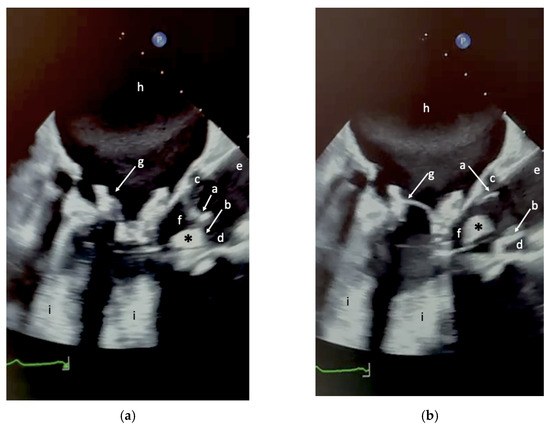

Review

Echocardiographic Assessment of Patients Undergoing Mitral Valve Repair

by Marco Rolando, Nadeem Elmasry, Federico Gobbi, Antonella Moreo, Nina Ajmone Marsan, Erberto Carluccio and Federico Fortuni

J. Cardiovasc. Dev. Dis. 2025, 12(12), 498; https://doi.org/10.3390/jcdd12120498 - 17 Dec 2025

Cited by 1 | Viewed by 1065

Mitral regurgitation (MR) is one of the most prevalent valvular disorders worldwide, with a growing burden driven by population aging and improved diagnostic capabilities. Understanding the mechanism of MR, whether primary, due to intrinsic valve abnormalities, or secondary, resulting from atrial or ventricular [...] Read more.

Mitral regurgitation (MR) is one of the most prevalent valvular disorders worldwide, with a growing burden driven by population aging and improved diagnostic capabilities. Understanding the mechanism of MR, whether primary, due to intrinsic valve abnormalities, or secondary, resulting from atrial or ventricular remodeling, is essential for optimal management. Echocardiography, particularly advanced modalities such as three-dimensional imaging and strain analysis, plays a central role in this process. It allows accurate quantification of MR severity, detailed characterization of valve and ventricular anatomy, and assessment of remodeling, all of which are critical for determining the optimal timing for intervention. Beyond diagnosis, echocardiography is indispensable in guiding therapy selection: it informs surgical planning by defining leaflet pathology for repair versus replacement strategies, and directs transcatheter interventions by guiding interatrial septal puncture, catheter orientation, and device deployment in real time. While surgery remains the gold standard for primary MR, transcatheter approaches including edge-to-edge repair and emerging mitral valve replacement are increasingly relevant, particularly in patients at high surgical risk or with complex anatomy. This review emphasizes the pivotal role of echocardiography in the pre-procedural assessment of MR, highlighting its ability to integrate anatomical, functional, and hemodynamic information to guide patient-tailored therapeutic strategies and optimize outcomes within a Heart Team framework. Full article

Show Figures

Figure 1